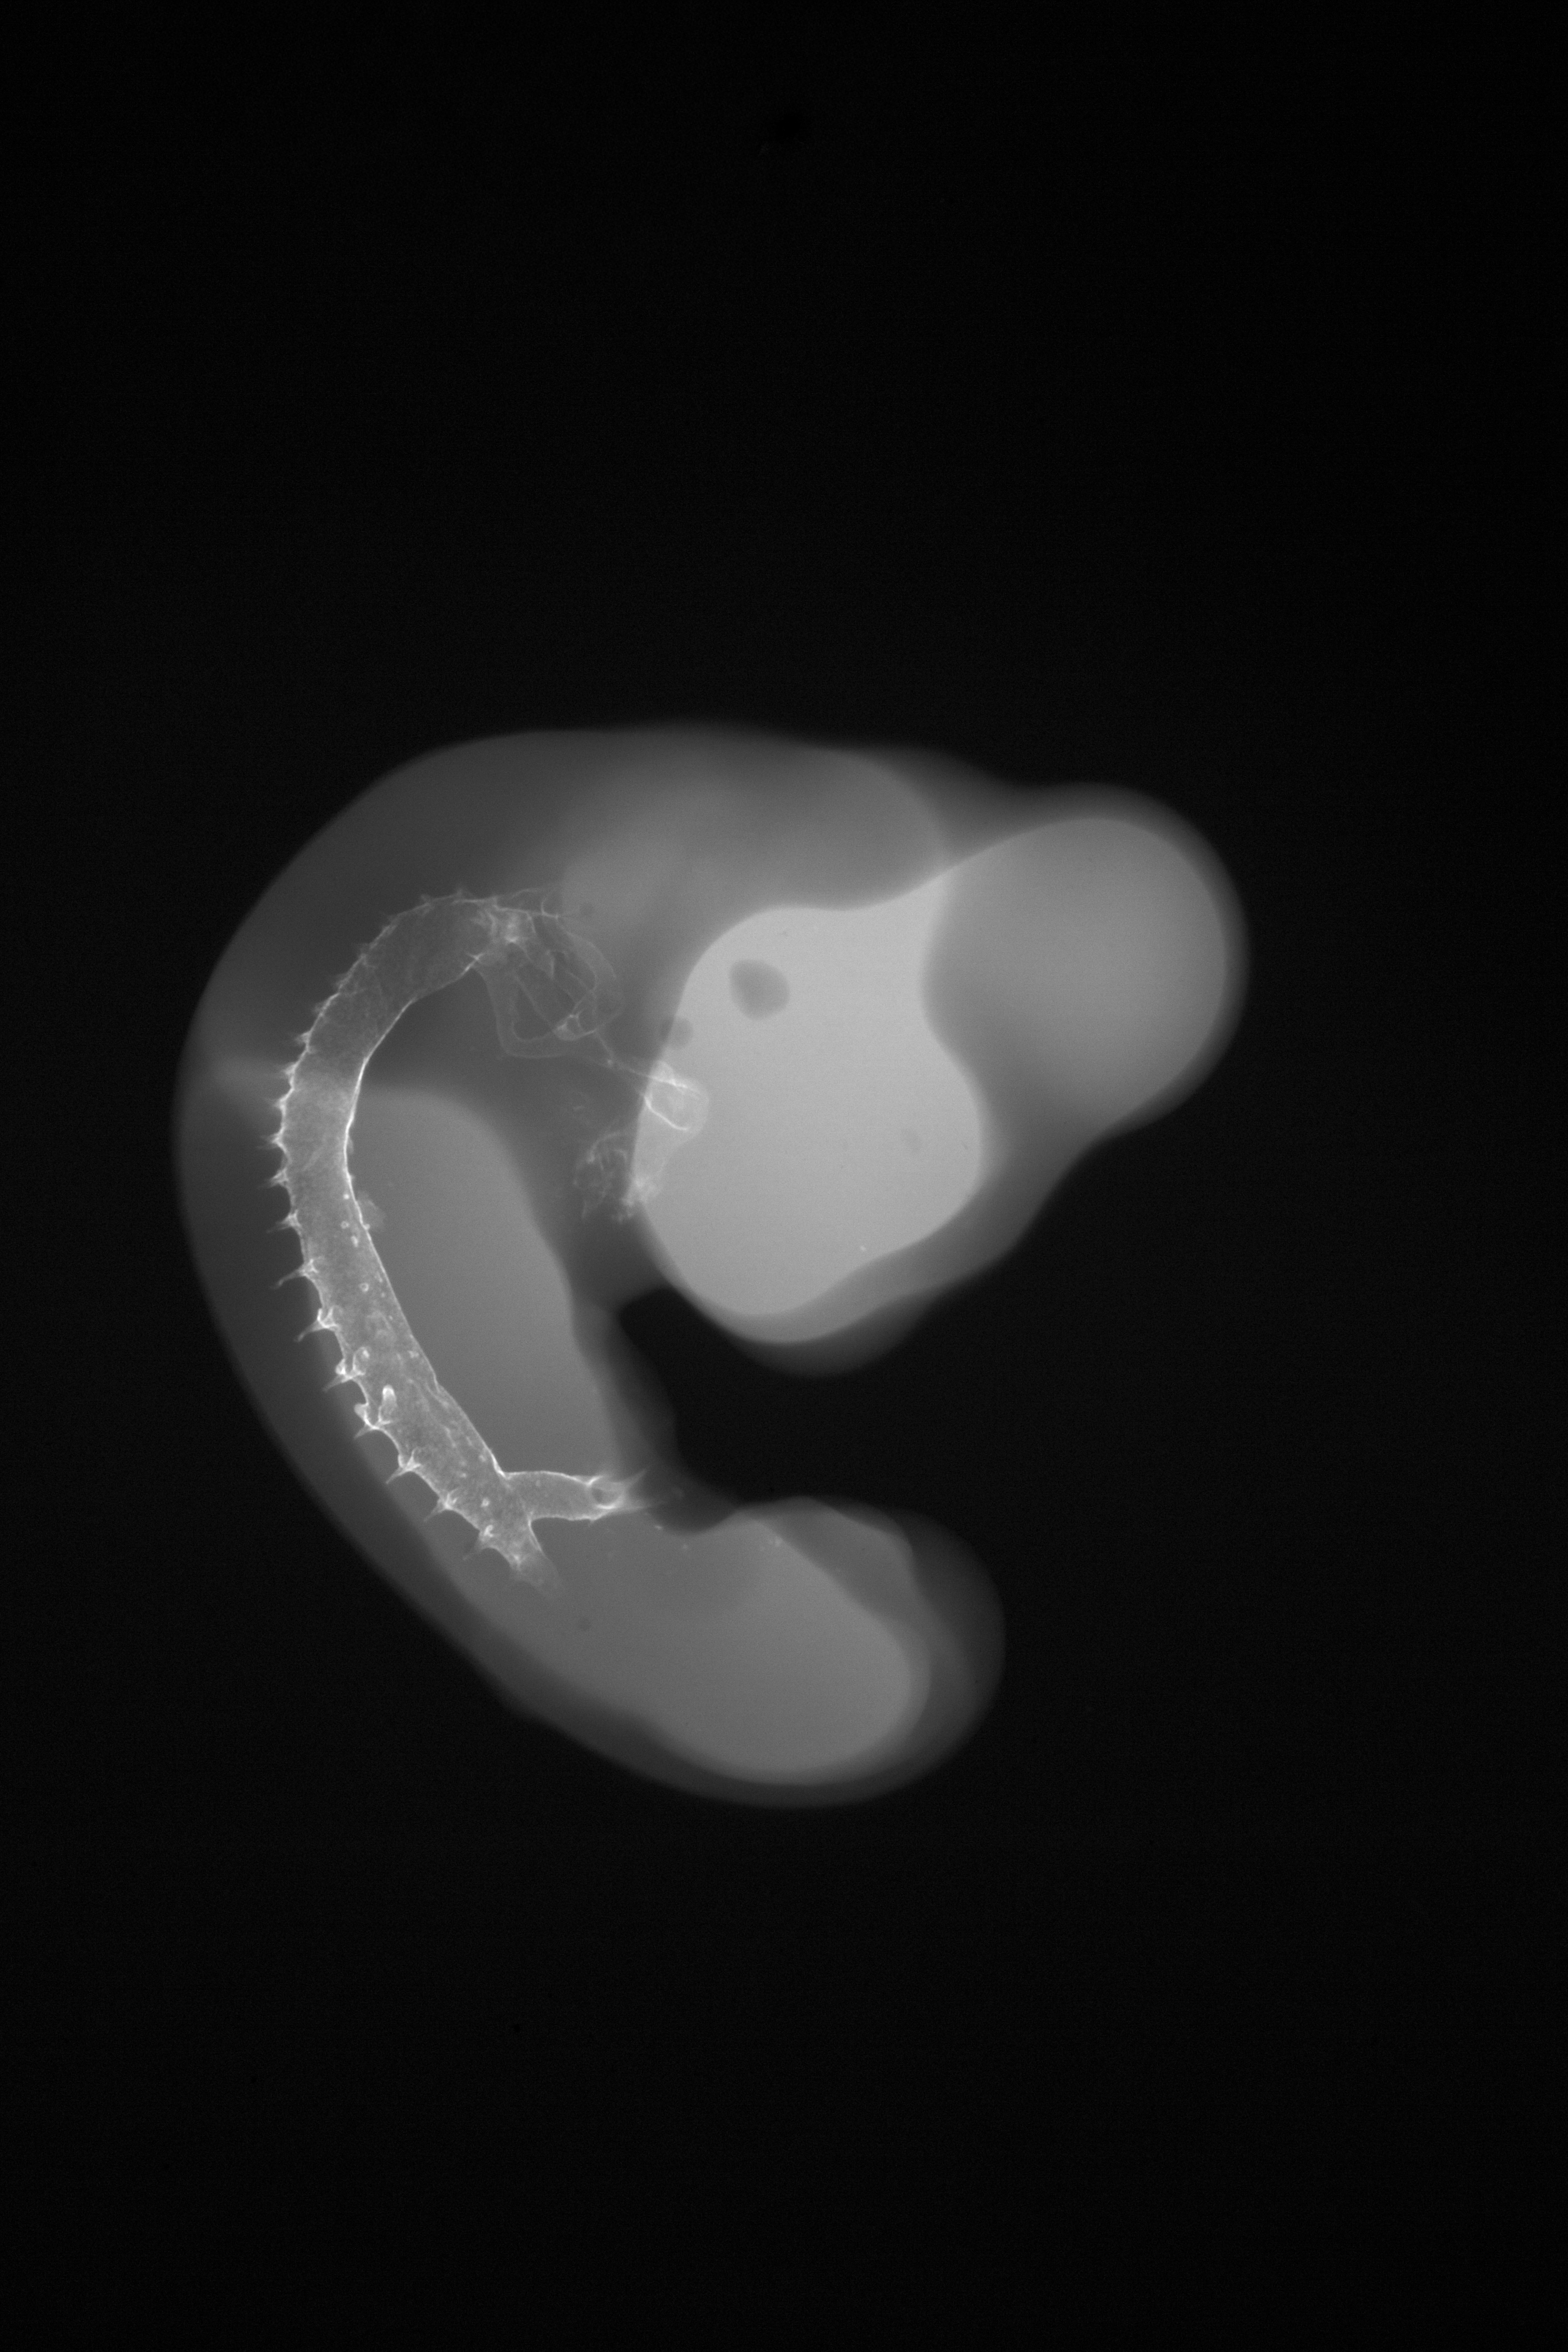

Chick Embryo Microangiography

Hamburger-Hamilton (HH) Stage 23 (approx. 4 days)

Drawing